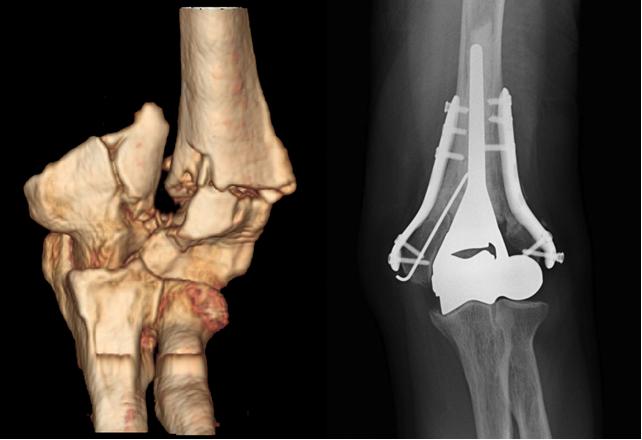

L’obiettivo dell’intervento di riparazione è di riportare il lembo di tendine strappato alla sua sede di inserzione all’osso della testa omerale e fissarvelo. Per far questo esistono diversi sistemi di ancoraggio, i più comuni sono rappresentati da “ancorette” di vari materiali che si avvitano o si impiantano a pressione nell’osso e a cui sono attaccati dei fili con i quali si sutura e si riporta in sede il tendine (fig. 6, 7, 8). I dispositivi utilizzati sono i più innovativi, e quando possibile utilizziamo ancorette di solo filo, riassorbibili o radiotrasparenti in modo da ridurre ulteriormente l’invasività chirurgica.